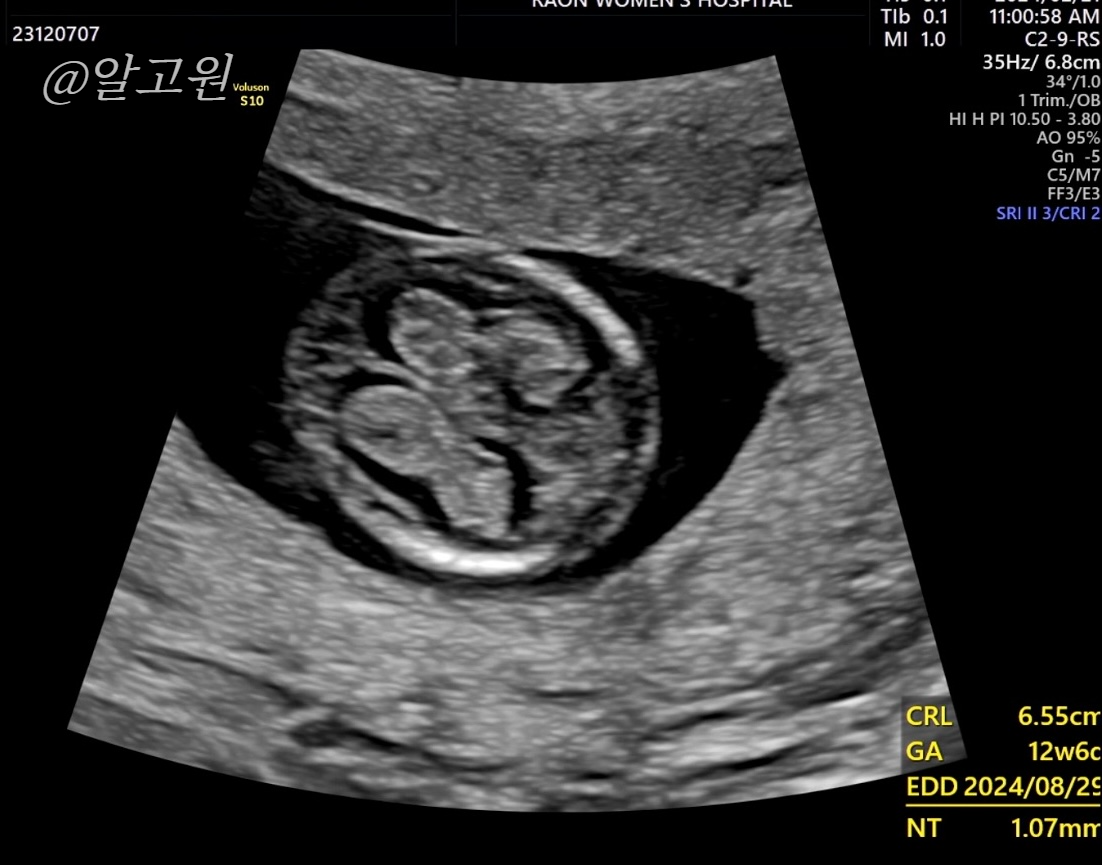

초음파로 목투명대, 척추와 뼈, 장기, 뇌 모양, 심장박동소리, 태반 위치 등

선생님께서 아주 꼼꼼히 봐주십니다.

다행히도 유동이는 정상,정상,정상!

목투명대도 1mm로 정상수치에 들었어요.

(3mm 이하면 정상, 이상일 경우 추가 검사진행)

** 12주에 과연 성별이 나올까?

확실하진 않지만 나옵니다!

의사선생님께 '혹시 성별은 언제 알 수 있을까요..?' 했더니

'지금!!!' 이라며 다리 사이를 짠하고 보여주셨는데요!

'이정도면은 딸 같은데..?' 라고 하시던 선생님ㅎㅎㅎㅎㅎ

아직 확실하지는 않다고 합니다ㅎㅎㅎ